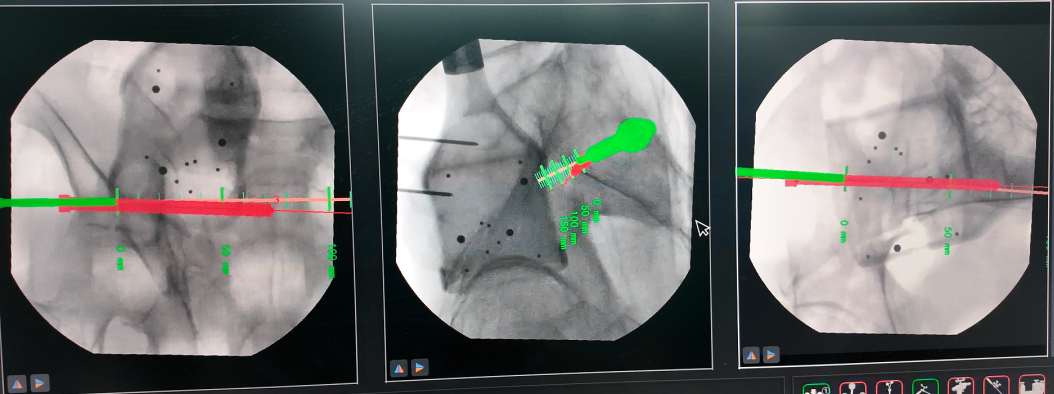

术中

机械臂按预设路径自动执行复位操作,精度高达毫米级,医生仅需通过几个微小切口置入内固定螺钉。